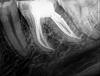

Kaiden Опубликовано 18 августа, 2012 Поделиться Опубликовано 18 августа, 2012 (изменено) Всем доброго дня. Примерно месяц назад начала сильно ныть левая нижняя сторона челюсти, боли преимущественно локализовались на левой нижней 6-ке. Она была ранее запломбирована, но нерв не удаляли. Обратился к врачу-стоматологу. Врач сняла пломбу, под пломбой был кариес, пульпит и периодонтит. Врач удалила нервы, пролечила каналы, поставила постоянную пломбу. Т. е. сначала (в день обращения) она заложила лекарство и поставила временную пломбу, потом через 3 дня - заменила лекарство и еще раз поставила временную пломбу и еще через 4 дня - постоянную. Но через 2-3 три дня после установки постоянной пломбы зуб опять начал болеть и болит уже три недели. Боль тупая, ноющая, когда усиливается - становится "давящей изнутри", распирающей. Боль может плавно (в течение нескольких часов) произвольно стихнуть или усилиться, мне не удалось заметить ничего, чтобы провоцировало ее усиление или ослабление. Когда боль еще сильнее усиливается, то начинает болеть вся левая сторона челюсти, появляется ощущение давления по ходу тройничного нерва от зуба к виску. Консультировался с несколькими другими стоматологами-терапевтами, они, глядя на снимок, все считают, что зуб пролечен хорошо, каналы полностью пройдены, воспаления у корней нет и т. д. Полагают, что боль, на самом деле, дает что-то другое - например, невралгия или мышцы/суставы челюсти, а я по каким-то причинам ощущаю ее в пролеченном зубе. Мне, честно говоря, не очень верится в невралгию или проблемы с мышцами и суставами. Более вероятным мне кажется, что что-то все-таки не так либо с пролеченным зубом (хотя все терапевты, смотревшие снимки, очень положительно оценили работу лечившего врача, так что тут тоже вероятность не очень высокая), либо с соседними зубами (они тоже под пломбами). Еще, возможно, интересный момент - через три дня после наложения временный пломбы, я случайно пожевал левой стороной челюсти вафельную конфету. В этот момент была резкая, острая, пронизывающая вспышка боли, а сама запломбированная 6-ка после этого еще пару дней ныла - такой же болью, какой ноет сейчас. Потом врач заменила лекарство, поставила вторую временную пломбу и боль стихла. Прикладываю прицельной снимок пролеченной 6-ки и ортопантограмму челюсти. Оба снимка сделаны 13 августа (т. е. через 15 дней после установки постоянной пломбы). Могут ли уважаемые стоматологи, подсказать, в чем может быть дело? А то я уже запарился бегать по врачам без особого толку Изменено 18 августа, 2012 пользователем Kaiden Ссылка на комментарий

ger_berra Опубликовано 19 августа, 2012 Поделиться Опубликовано 19 августа, 2012 Верхняя 6-ка слева с пломбой,расположенной близко к"нерву",может давать симптоматику пульпита.По снимку нижняя 6-ка сделана очень хорошо,но в ней может быть пропущенный корневой канал в медиальном(переднем) корне.Он тоже может так себя проявлять.Микроскоп даст ответ на все вопросы.Сначала надо заглянуть под пломбу в 26 зубе,потом только лезть в 36. Ссылка на комментарий

Kaiden Опубликовано 22 августа, 2012 Автор Поделиться Опубликовано 22 августа, 2012 Верхняя 6-ка слева с пломбой,расположенной близко к"нерву",может давать симптоматику пульпита.По снимку нижняя 6-ка сделана очень хорошо,но в ней может быть пропущенный корневой канал в медиальном(переднем) корне.Он тоже может так себя проявлять.Микроскоп даст ответ на все вопросы.Сначала надо заглянуть под пломбу в 26 зубе,потом только лезть в 36. Ясно, спасибо за ответ.Пока сделал КТ - на томограмме 5-го канала у 6-ки не видно, никаких проблем с соседними зубами по снимку также не вырисовывается.Видимо, остается действительно либо снимать пломбы и смотреть, что под ними, либо предполагать наличие каких-то проблем с суставами/мыщцами или невралгии. Ссылка на комментарий